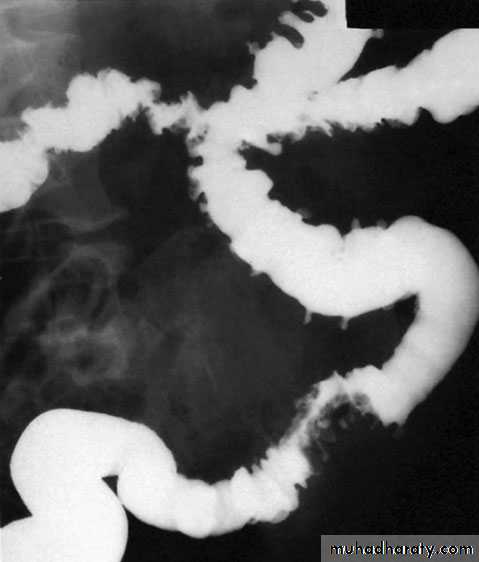

DiverticulosisIt is important to distinguish between diverticulosis, which maybe asymptomatic, and clinical diverticular disease in which thediverticula are causing symptoms. On histological investigation,the diverticulum consists of a protrusion of mucous membranescovered with peritoneum. There is thickening of the circularmuscle fibres of the intestine, which develops saw-tooth appearance on barium enema

Barium enemas and sigmoidoscopy are usuallyreserved for patients who have recovered from an attack of acute diverticulitis, for fear of causing perforation or peritonitis. Watersoluble contrast enemas may, however, be helpful in sorting out patients with large bowel obstruction. In the acute situation, it is good at detecting intraluminal changes and leakage. The sensitivity for this is of the order of 90%. Barium radiology is carried out to exclude a carcinoma and to assess the extent of the disease.

Where the sigmoid colon is thickened and narrowed, a ‘sawtooth’ appearance may be seen. Some strictures can be very difficult to distinguish by radiology alone and, in those circumstances, colonoscopy will be necessary to rule out a carcinoma. Vesicocolic fistulae should be evaluated with cystoscopy and biopsy in addition to colonoscopy. Contrast examinations may show the fistula itself. The differential diagnosis for vesicocolic fistulae (and other fistulae) includes cancer, radiation damage, Crohn’s disease (CD), tuberculosis and actinomycosis.